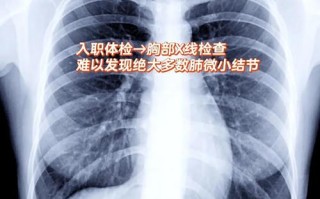

AI读片肺结节过度诊断怎么办? 人工智能

AI读片肺结节过度诊断怎么办?

您提出的“人工智能读片肺结节过度”是一个非常精准且关键的问题,是当前AI在医疗影像领域应用中最受关注的挑战之一,这里的“过度”可以从两个层面来理解:技术层面:假阳性(False Positive)过高...